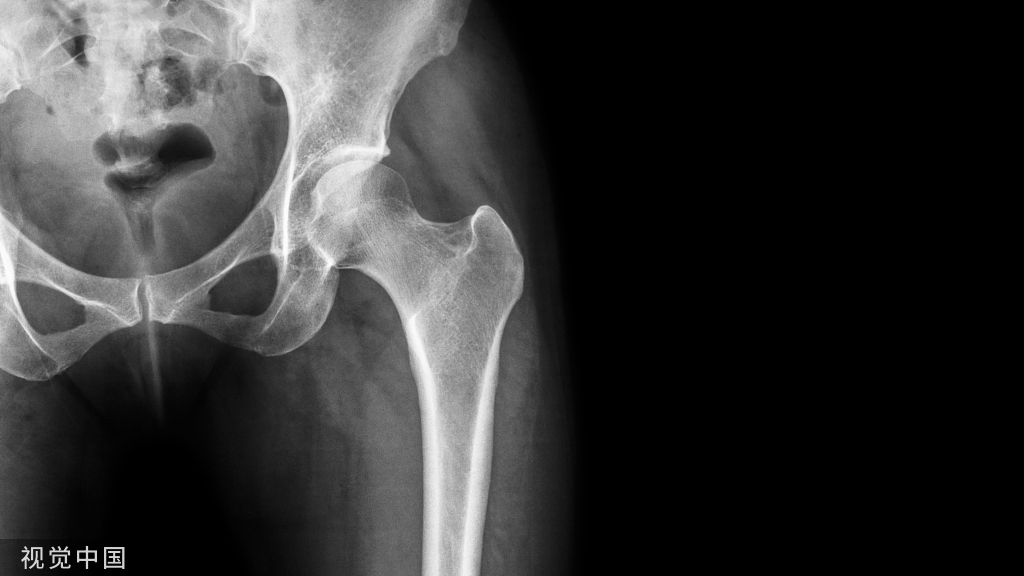

X线表现与测量

足的x线测量对于进一步了解拇外翻的病理及设计手术方案是非常重要。负重足的基本功能,很多足的畸形在负重状态下可以表现得更清楚。一些测量指标在负重和非负重状态下可以明显不同。足部各种x线测量一般都是在足负重位摄片下完成。手术前常规需要拍摄患足负重位、前后位和侧位,根据需要拍摄足的非负重位内旋斜位和籽骨轴位。

1:前后位观察和测量拇外翻角(HAA)  :拇趾跖骨中轴线与近节趾骨中轴线之夹角。正常为15°~20°

第1、2跖骨间夹角(IMA):  第1、2跖骨中轴线之夹角。正常为9 °拇外翻时此角通常大于正常。

拇外翻的分度与分类足踝外科学中Mann将拇外翻分为轻、中、重三度1.轻度  第1跖骨头内侧突出并有疼痛。HAA<30°,一部分畸形可由于趾骨间关节外翻引起,跖趾关节一般是适合的,IMA通常<13°,胫侧籽骨一般位于正常位置或有轻度移位,位于位置4。2.中度  拇趾外偏挤压第2趾,拇趾一般有旋前畸形,HAA30°~40°,IMA通常13°~ 16°,胫侧籽骨有明显脱位,位于位置6~7。3.重度  拇指外偏挤压第2趾形成骑跨趾,拇趾有中重度的旋前畸形,HAA>40°,IMA通常>16°,第2趾跖骨头下形成转移性跖骨痛。胫侧籽骨脱位于跖骨头腓侧缘外。